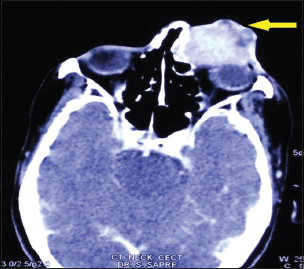

A 50-year-old female with no known comorbidities presented with epiphora left eye, blood in tears, and swelling over left lacrimal sac site of 2 months' duration. Clinical examination revealed a large, erythematous, lobulated 8 cm × 5 cm firm swelling fixed to underlying structures extending from left medial canthus to lower cheek area and left alae of nose covering the entire left eye with resultant restricted eye opening and no perception of light [Figure 1]. Right eye was normal with a visual acuity of 6/12. Computed tomography (CT) scan face and neck showed a 6.5 cm × 5.8 cm × 5.3 cm mass lesion left pre-orbital region eroding the medial wall of left maxillary sinus, left nasal cavity, nasal septum, anterior ethmoidal sinus and left orbit. No intracranial extension was seen. Multiple lymph nodes were seen at Level II and III [Figure 2]. Whole body positron emission tomography scan showed a localized disease without systemic dissemination [Figure 3].

| Figure 2 Computed tomography scan face and neck showing a mass lesion left preorbital region, eroding the medial wall of left maxillary sinus, extending into left nasal cavity, nasal septum, anterior ethmoidal sinus, and left orbit (yellow pointer)